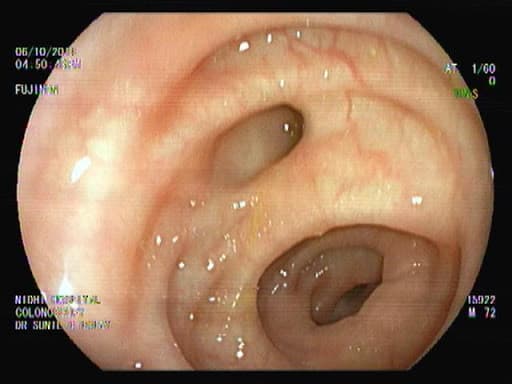

Colonoscopy is a common, safe test to examine the lining of the large bowel. During a colonoscopy, doctors who are trained in this procedure (endoscopists) can also see part of the small intestine (small bowel) and the end of the GI tract (the rectum). This procedure is often done under sedation to assure maximal patient comfort.

During a colonoscopy, the endoscopist uses a flexible tube, about the width of your index finger, fitted with a miniature camera and light source. This device is connected to a video monitor that the doctor watches while performing the test. Various miniaturized tools can be inserted through the scope to help the doctor obtain samples (biopsies) of the colon and to perform maneuvers to diagnose or treat conditions.

Colonoscopy can detect and sometimes treat polyps, rectal bleeding, fissures, strictures, fistulas, foreign bodies, Crohn’s Disease, and colorectal cancer.